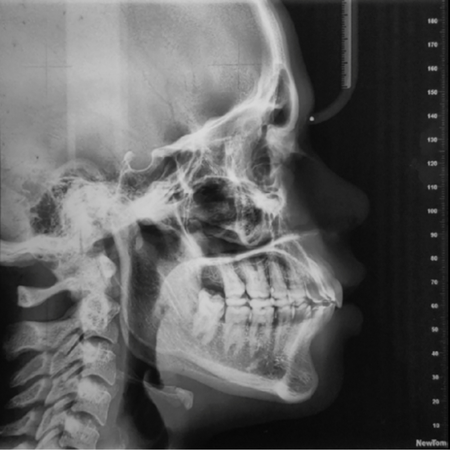

INTRODUÇÃO: O tipo mais frequente de hipercementose, quando moderada ou intensa, deixa o dente com a forma de clava. Nesses casos, não se deve movimentá-lo ortodonticamente, pois o formato da raiz dificulta ou impede a ação de forças no ligamento periodontal, que induziria os mecanismos biológicos da movimentação osteodentária. METODOLOGIA, RESULTADOS E DISCUSSÃO: Para diagnosticar se a hipercementose em forma de clava é moderada ou intensa, o critério proposto é traçar uma tangente na superfície do terço cervical do dente e observar se o contorno externo da...

INTRODUÇÃO: O tipo mais frequente de hipercementose, quando moderada ou intensa, deixa o dente com a forma de clava. Nesses casos, não se deve movimentá-lo ortodonticamente, pois o formato da raiz dificulta ou impede a ação de forças no ligamento periodontal, que induziria os mecanismos biológicos da movimentação osteodentária. METODOLOGIA, RESULTADOS E DISCUSSÃO: Para diagnosticar se a hipercementose em forma de clava é moderada ou intensa, o critério proposto é traçar uma...

INTRODUCCIÓN: El tipo más común de hipercementosis, cuando es moderada o severa, deja el diente en forma de maza. En estos casos, no se debe realizar movimiento ortodóncico, ya que la forma de la raíz dificulta o impide la acción de fuerzas sobre el ligamento periodontal, lo que induciría los mecanismos biológicos del movimiento dental ortodóncico. METODOLOGÍA, RESULTADOS Y DISCUSIÓN: Para diagnosticar si la hipercementosis en forma de maza es moderada o severa, el criterio...

INTRODUCTION: The most common type of hypercementosis, when moderate or severe, leaves the tooth in the shape of a club. In these cases, orthodontic movement should not take place, as the shape of the root hinders or prevents the action of forces on the periodontal ligament that would induce the biological mechanisms of osteodental movement. METHODOLOGY, RESULTS AND DISCUSSION: To diagnose whether club-shaped hypercementosis is moderate or severe, the proposed criterion is to draw a tangent...